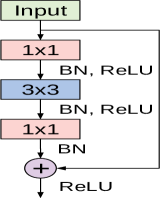

The cornerstone of the ShuffleNet model is the ShuffleNet unit depicted in Figure 5. It is a bottleneck residual module in which the convolutional layer is replaced by a depthwise separable convolution as in [42]. Also, the first convolutional layer is replaced by a pointwise group convolution followed by a channel shuffle operation. The second pointwise group convolutional layer is used to retrieve the channel dimension to match the left path of the unit. The overall ShuffleNet network is composed of a stack of these units grouped into three different stages along with other conventional convolution and pooling layers.